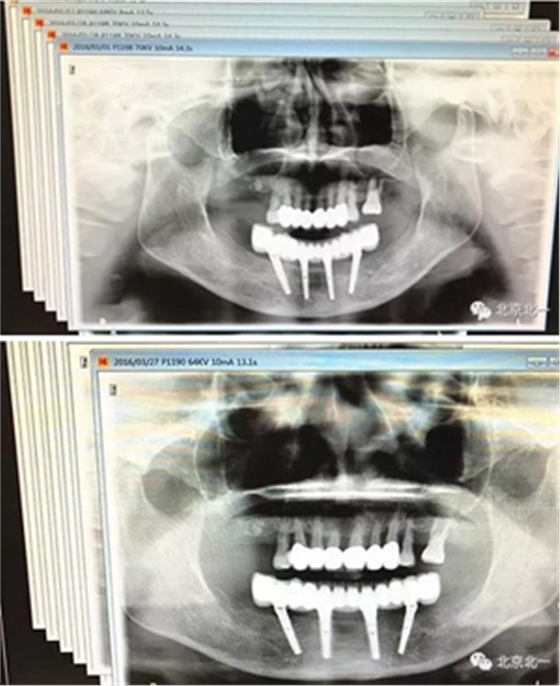

圖二十三:有圖有真相。

圖二十四:2017年11月復(fù)查時照片,植體很穩(wěn)定, 無骨吸收。